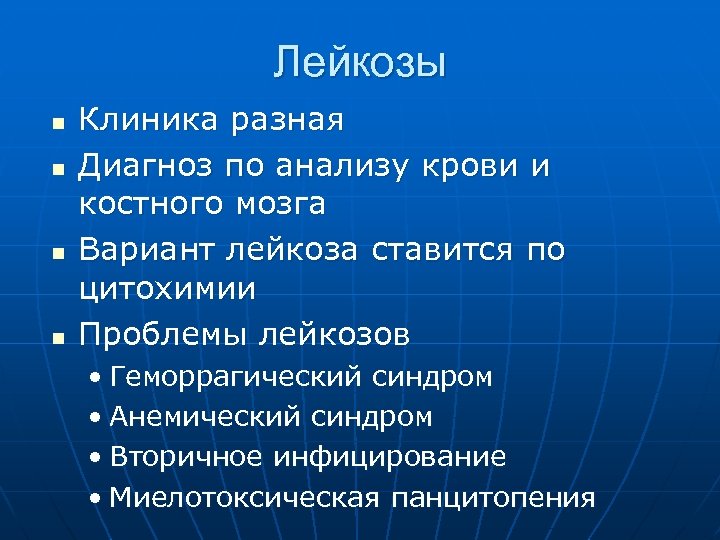

Лейкозы n n Клиника разная Диагноз по анализу крови и костного мозга Вариант лейкоза ставится по цитохимии Проблемы лейкозов • Геморрагический синдром • Анемический синдром • Вторичное инфицирование • Миелотоксическая панцитопения